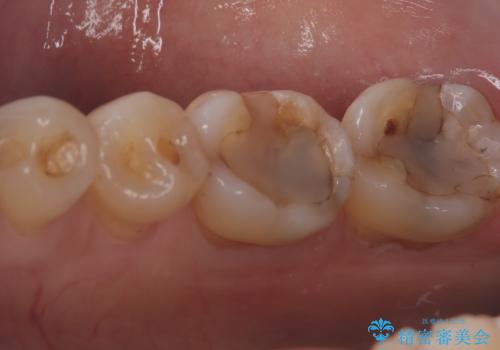

今回残存歯質量から破折のリスクを説明し、クラウンでのやり替えも提案しましたが歯質切削量が多くなることから一度インレーで様子を見ることとなりました。

セラミックインレーセット時はラバーダム防湿を行っています。